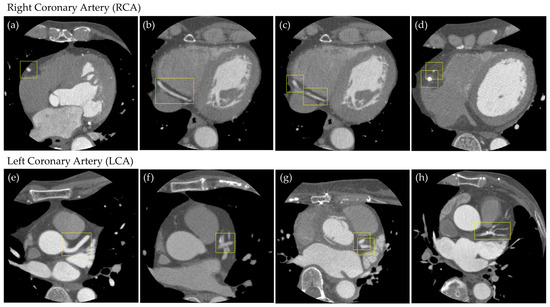

- We propose an annotation method that defines bounding boxes for major coronary arteries (RCA, LCA-LAD, and LCA-CX) in cross-sectional CCTA slices, enabling systematic and reproducible labeling.

2.3. Supervised Data Creation

Object Detection